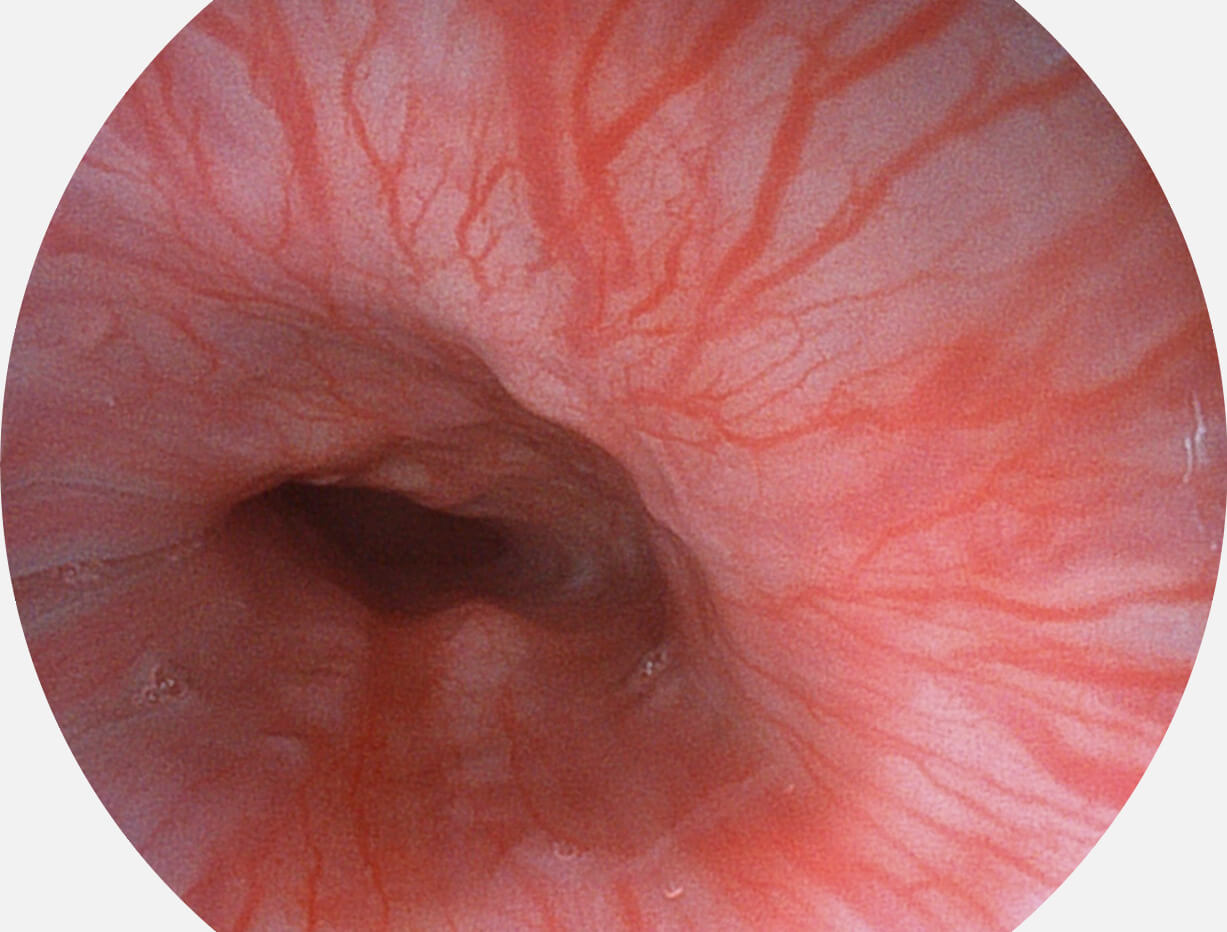

• 白光图像 SFI图像